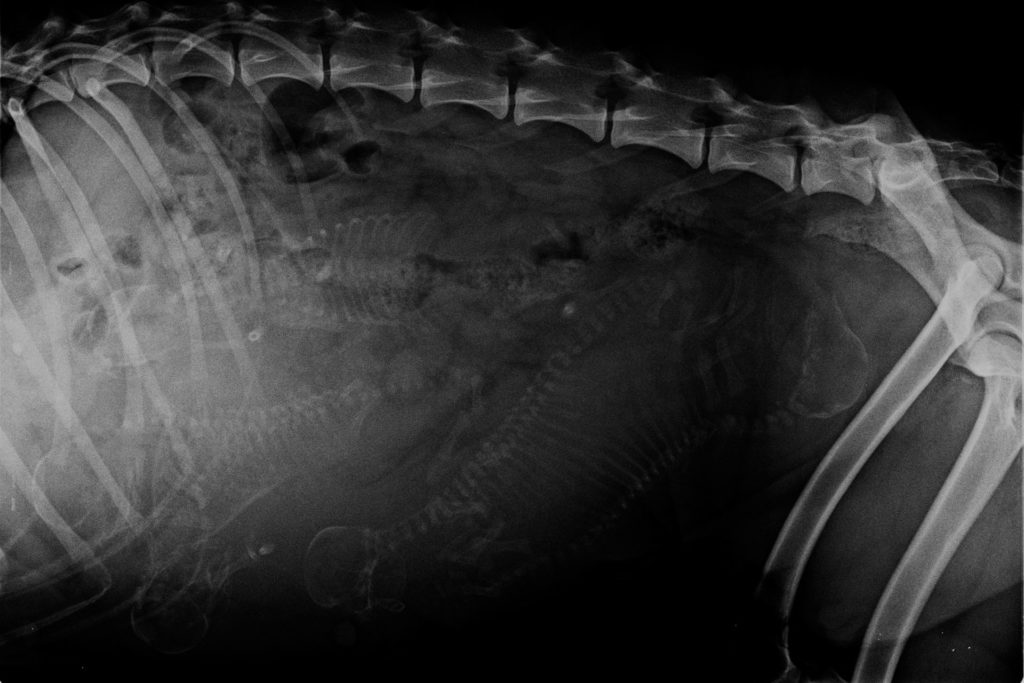

This morning we went to the vet clinic with Nukka for a final checkup, the second herpes vaccination and had her x-rayed. Nukka stayed most of last weeks with her family and so I was quite unsure about the number and size of her pups. The ultrasonography we did some […]